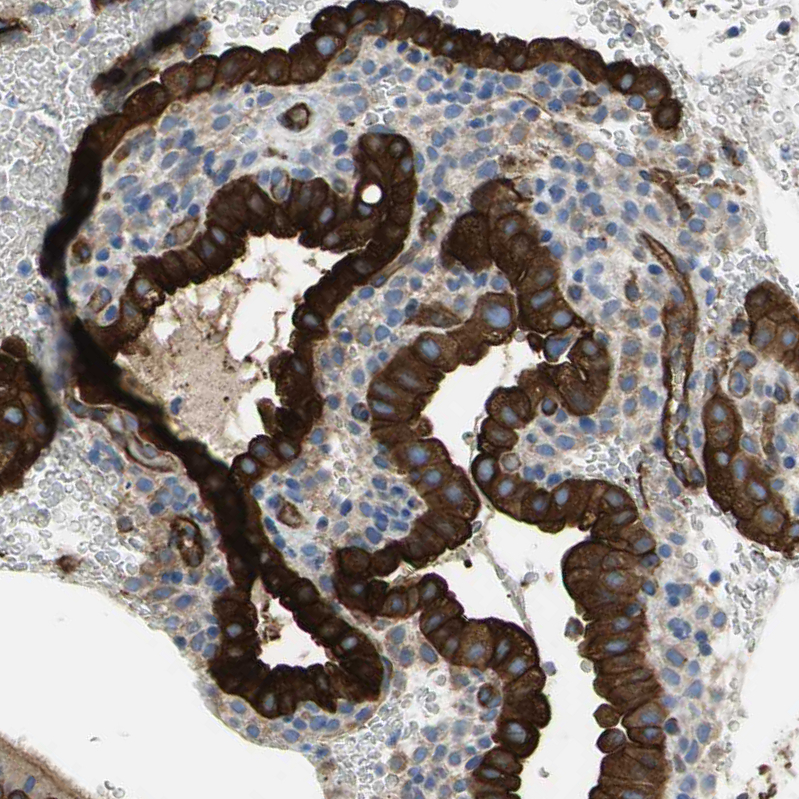

Immunohistochemistry analysis in human prostate and skeletal muscle tissues using HPA004747 antibody. Corresponding FLNB RNA-seq data are presented for the same tissues.